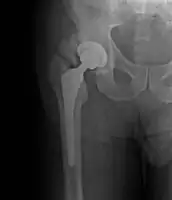

- Locations

- Hip most common - typically after ORIF (52% any grade, 19% Grade III-IV) or THA (43% any grade, 9% Grade III-IV)

- Elbow common with burn injuries

- Other major joints sometimes affected